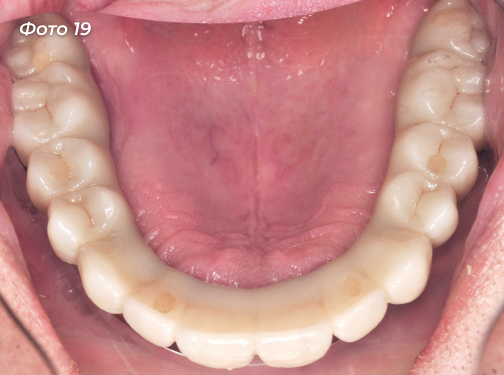

Установлены постоянные конструкции на верхней и нижней челюстях (Фото 18, 19, 20, 21).